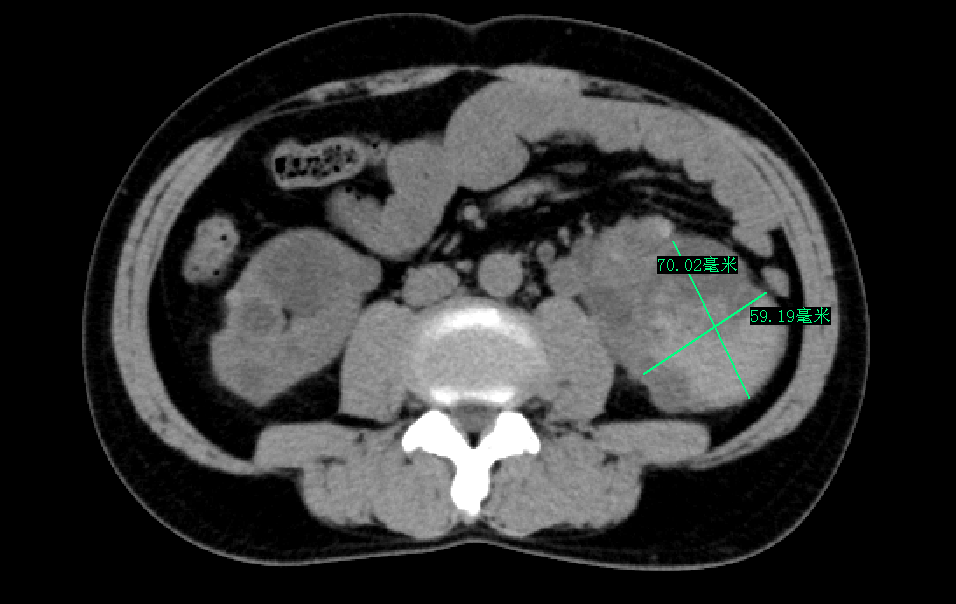

三个月前,林先生 毫无征兆出现了肉眼血尿 ,且持续多日不见好转,这才让他慌了神,急忙再次来到我院就诊。完善双肾 CT平扫提示:双侧多囊肾, 左肾较大囊肿已达7厘米。 经过对症处理病情曾好转,但入院一周前血尿再次复发,自行服药无效后,林先生决定重返医院泌尿肾病科,寻求根治。